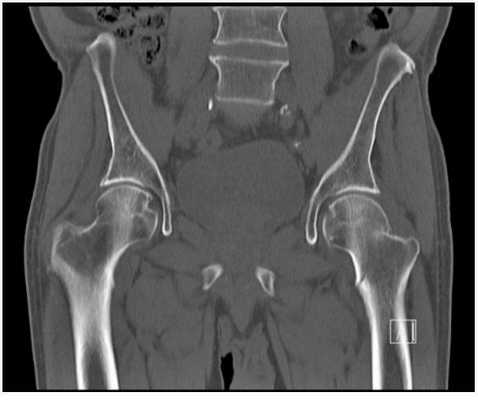

На снимке показан пример ишиофеморального импинджмента в хронической форме. Пациент - женщина в возрасте 60 лет. Жалобы - постоянные болевые ощущения в тазобедренных суставах, наиболее проявляющиеся в правом.

Гипертрофия седалищных бугристостей, ведущая к значительному сужению ишиофеморальных пространств; наблюдается деформация, отеки, несущественные скопления жидкости в квадратных бедренных мышцах (максимально заметные справа), неравномерная атрофические изменения с характерной жировой инфильтрацией.